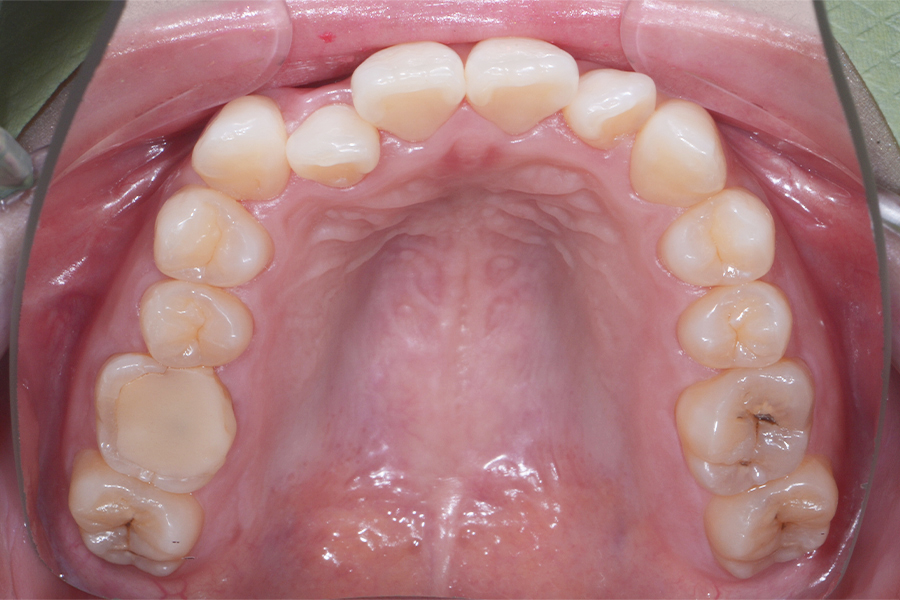

• 治療後

期間 治療期間8か月

費用 治療費20万(別途調整料)

治療内容 上顎ラビアル矯正(表側矯正)

治療に伴うリスク 後戻り